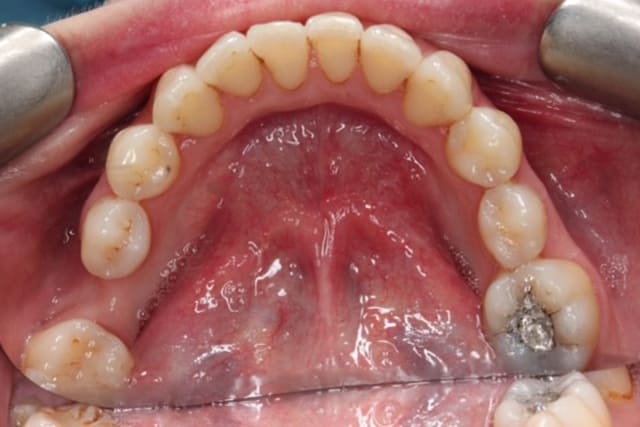

Dental Hygienist service before image – Bayswater Dental Clinic